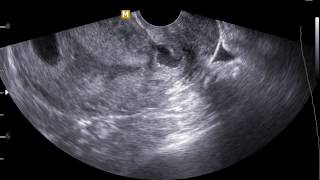

Рождение телёнка #обзор #обзоры #животные #врач #ветеринар #корова #роды #наука #медик #медицина